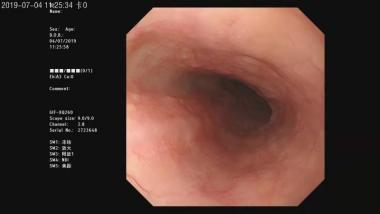

②结肠镜

结肠镜可以观察包括直肠、乙状结肠、降结肠、 横结肠、升结肠、盲肠至回肠末端的肠道黏膜,主要用于诊断结、直肠炎症,良性肿瘤,息肉,憩室等疾病